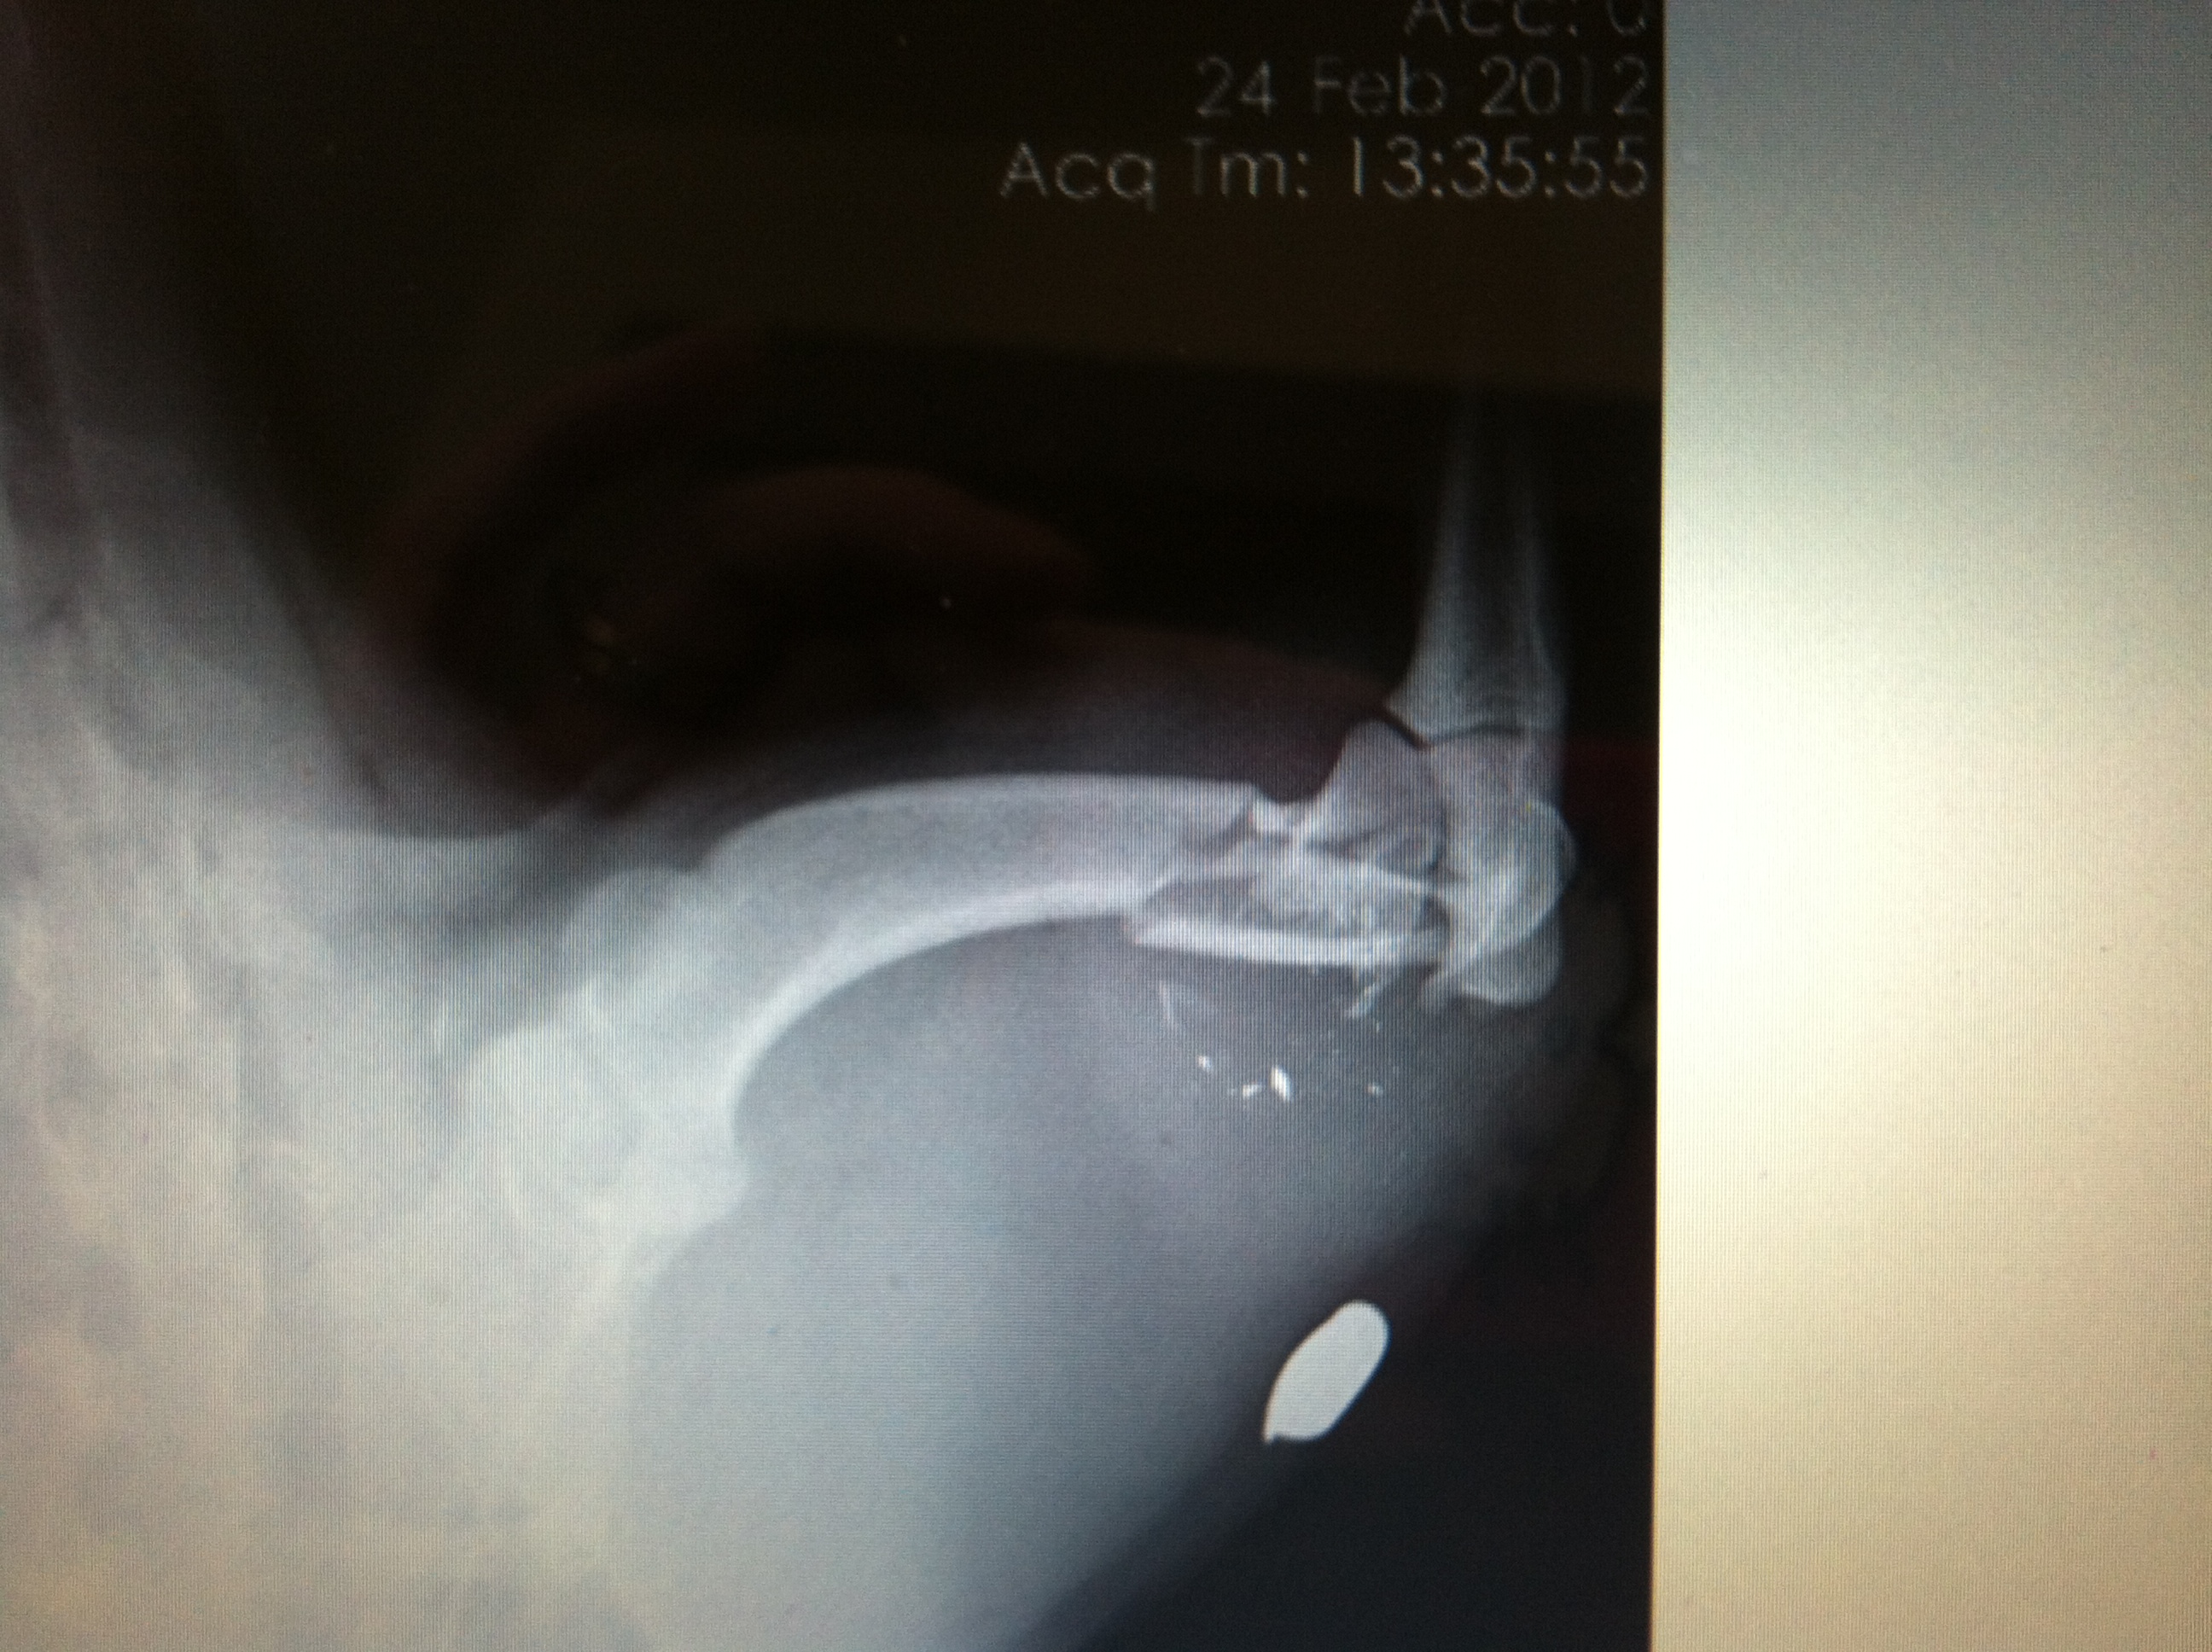

To my surprise, she was a very lucky kitten! (considering she was only 2 pounds and lived through such a trauma) She had no use of her back hind leg. I was expecting to find a bad fracture in her rear limb, but again, she surprised me:

The only thing of significance on this x-ray is a growth plate injury (if I were more computer savvy I would put an arrow on it, but alas, I am not). Bone growth occurs at specific places (growth plates) in long bones, and damage to these areas can result in malformation of the limbs. Fixing this injury would require surgery. Since she was so tiny and just suffered a major injury, surgery needed to be put on hold.

The weird thing about her x-ray was that it did not explain her degree of injury. Even animals with a complete fracture will show some movement in the limb even though they can’t walk on it. This told me that she had significant nerve damage and may lose the leg:(